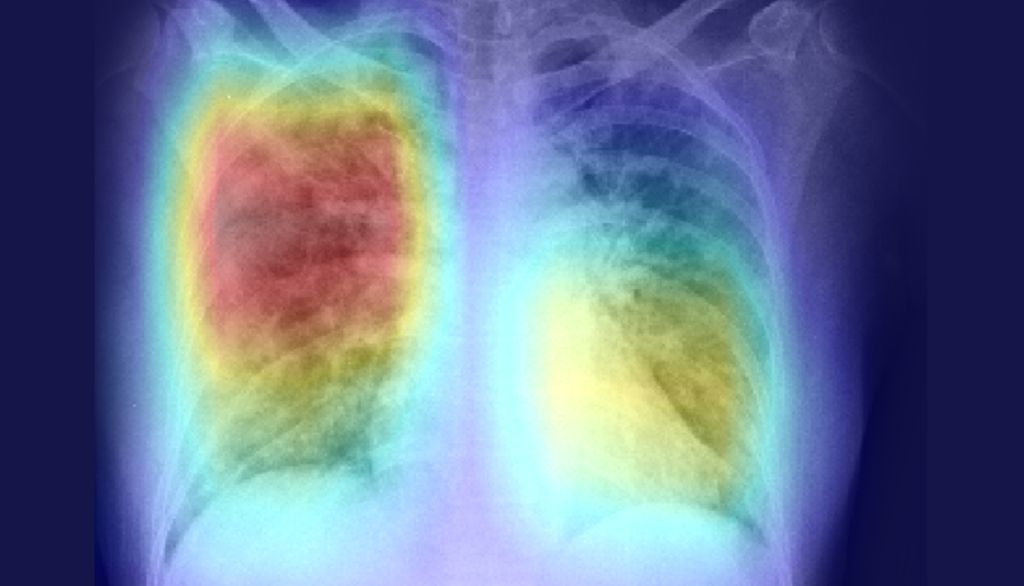

Ingénieur biomédical de formation, le professeur Duchesne a acquis une expertise dans l'art de faire parler les images médicales, notamment les scans de cerveau. La pandémie l'a conduit à transposer cette expertise aux problèmes qui se posent maintenant dans les unités de soins intensifs. «Nous croyons que les radiographies pulmonaires contiennent des informations qui peuvent nous renseigner sur la façon dont évoluera la COVID-19 chez un patient», avance le chercheur.

Simon Duchesne et ses collaborateurs croient que les radiographies pulmonaires contiennent des informations qui peuvent nous renseigner sur la façon dont évoluera la COVID-19 chez un patient.

Pour créer cet algorithme, le professeur Duchesne et ses collaborateurs ont d'abord utilisé 225 000 radiographies de personnes souffrant d'une pneumonie causée par une infection d'origine bactérienne ou virale. «L'algorithme a "appris" à associer des particularités de ces images de poumon à la description qui en a été faite par des experts en radiologie», résume-t-il.

L'algorithme a été mis à l'essai sur une centaine de radiographies pulmonaires, provenant du domaine public, qui montrent des patients atteints de COVID-19. «Notre système sait maintenant quelles particularités d'une radiographie pulmonaire il doit surveiller pour détecter une pneumonie chez une personne atteinte de COVID-19. Les particularités qui détermineront le degré de succès d'une ventilation sont probablement si subtiles qu'elles échapperaient à l’œil nu. Nous espérons que l'algorithme pourra les détecter», explique le professeur Duchesne.